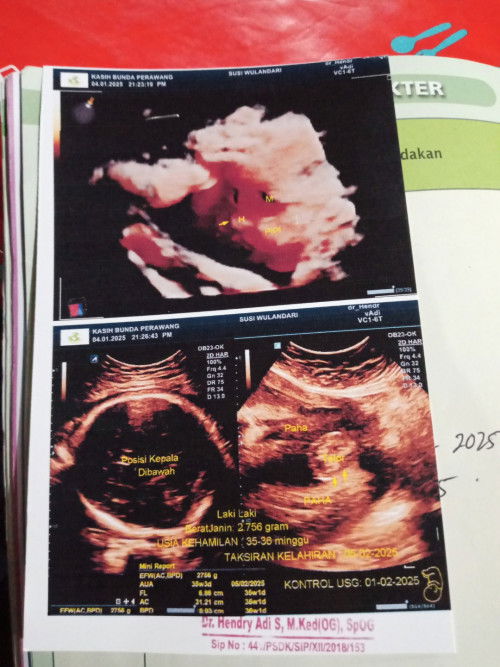

Mau nanya nih bun seputaran usg 4d, saya kemaren habis usg 4d, kata dokter sih normal semua bun, tpi pas saya perhatikan hasil usgnya bibirnya kok kyk bercelah yah bun bikin overthinking ajah bun😭😭Menurut bunda ini normal gak yah kata dokter semuanya normal,, yallah smoga inii hanya fikiranku saja smoga anakku sehat sempurna yallah #Sharingdong_Bund #bantujawab